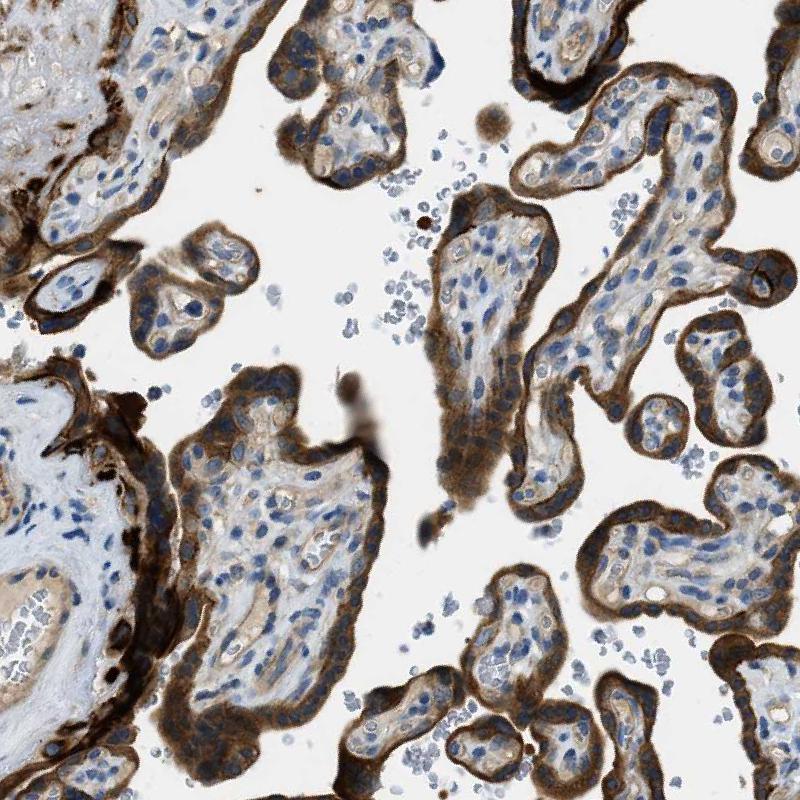

Immunohistochemical staining of human urinary bladder shows moderate to strong cytoplasmic / membranous positivity in urothelial cells.